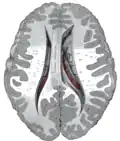

The caudate nuclei are near the center of the brain, sitting astride the thalamus. There is a caudate nucleus in each hemisphere of the brain. Each nucleus is C-shaped, with a wider "head" (caput in Latin) at the front, tapering to a "body" (corpus) and a "tail" (cauda). Sometimes a part of the caudate nucleus is called the "knee" (genu).[6] The caudate head receives its blood supply from the lenticulostriate artery; the tail of the caudate receives its blood supply from the anterior choroidal artery.[7]

The head and body of the caudate nucleus form part of the floor of the anterior horn of the lateral ventricle. The body travels briefly towards the back of the head; the tail then curves back toward the anterior, forming the roof of the inferior horn of the lateral ventricle. This means that a coronal section (on a plane parallel to the face) that cuts through the tail will also cross the body and head of the caudate nucleus.